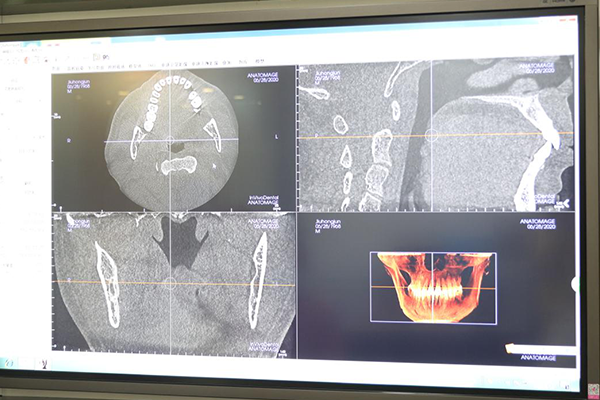

在经过一系列精确的数字化CBCT影像检测后,刘洪军的数字化精确种植牙手术进行得十分顺利。“种牙前我没有什么好担心的,麦芽的医生和护士都很专业,服务也十分热情,进行的每一步操作都有明确详细的说明,手术中我也没有任何感觉,很快就种好了。”种完牙的刘洪军一脸轻松:“种牙其实不贵,但要选对。以后我的种植牙都交给麦芽了!大品牌、大专家、种牙有保障,放心更暖心。”